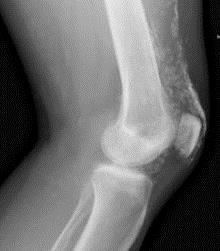

Xəstəlik əzələ sindromu (miasteniya, miologiya) artalgiya, qızdırma, dərinin zədələnməsi, ödemlərlə kəskin və yarım kəskin başlayır. Sonralar xəstəlik residivləşən gedişli hal alır. Bütün xəstələrdə sakitlik, hərəkət, təzyiq altında mialgiya şəklində skelet əzələlərinin zədələnməsi, əzələ zəifliyinin artması müşahidə olunur. Çiyin və çanaq qurşağının əzələləri bərkiyir, həcmi böyüyür, hərəkəti aktivliyi pozulur. Xəstə sərbəst otura ətraflarını və başını qaldıra bilmir. Proses əhəmiyyətli dərəcədə artdıqda xəstə tam hərəkətsizləşir. Patoloji prosesi mimiki əzələlərə nüfuz etməsi üzün maska şəkli almasına, udlaq əzələlərinə nüfuz etməsi disfagiyaya, qabırğarası əzələlərə və diafraqmaya yayılması tənəffüsün pozulmasına, ağciyərin həyat tutumunun azalaması hipoventilyasıya və tez-tez pnevmoniyaya səbəb olur. Gözləri hərəkət etdirən əzələlər zədələnərək, diplopiya (2 görmə) çəp gözlük, iki tərfli göz qapağının düşməsi (ptoz) əlamətləri ortaya çıxa bilər. Xəstəliyin ilk etaplarında əzələlər ağrılı və ödemlidir. Sonralar isə distrofiyaya və autolizə məruz qalmış əzələ liflərində miofibroz, atofiya, kontraktura, nadirən kalsinoz inkişaf edir. Kalsinoz həmçinin dərialtı birləşdirici toxumada yaranır və rentgenoloji tətqiqatlarda aşkar olunur. Elektromioqrafiyada dəyişiklər qeyri spesifikdir. Dərinin zədələnməsi müxtəlif şəkillərdə — eritrematoz, papulyoz, bulyoz səpkilər, purpura, telangioektaziya, hiperkeratoz, hiperpigmentasiya, depigmentasiya ilə təzahür edir. Səpkilər halında qaşınmada olur. Periorbital (gözətrafı) ödem, purpura dermotizit eynəyi xarakterikdir. Hərəkət zamanı poliatralgiya və oynaq hərəkətinin (ankoloza qədər) məhdudlaşması əzələlərinin zədələnməsi ilə əlaqədardır. Miokardın iltihabı və distrofik zədələnməsi müşahidə olunur ki, bu da davamlı taxikardiya, labil nəbz, artirial hipotenziya, ürəyin sola doğru böyüməsi, tonların karlaşması, zirvədə sistolik küylə büruzə verir. EKQ-də voltajin kiçilməsi, oyanıqlığın və keçiriciliyinin pozulması, ST segmentin çökməsi, T dişinin parçalanması kimi dəyişiklər aşkar olunur. Diffuz miokardit zamanı ağır ürək çatışmazlığı mənzərəsi yaranır. Xəstələrdə Reyno sindromu müşahidə olunur. Xəstələrin demək olar ki, yarısında mədə — bağırsaq traktı prosesə qoşulur. Anoreksiya, qarında ağrı, qastroentrokolit simptomlar qida borusu yuxarı şöbəsində hipotoniya təyin olunur. Mədə və bağırsaq selikli qişasının zədələnməsi prosesi gedə bilər ki, bu özünü nekroz, ödem, hemoragiyadan, ağır mədə bağırsaq qanaxmalarına, mədənin, bağırsağın perforasiyasına qədər zədələnmələrlə göstərir.